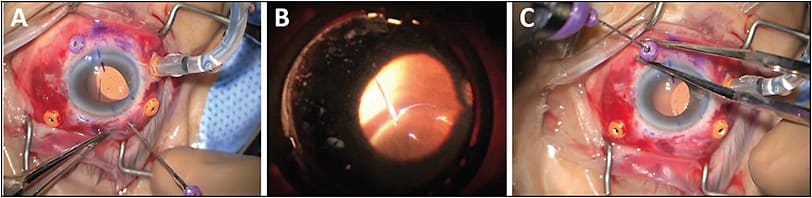

Once the vitrectomy is complete, the dislocated IOL should first be explanted. As a right-handed surgeon, I make a corneal paracentesis at 2 o’clock and a triplanar corneal wound (use a 2.75-mm keratome and slightly extend) at 11 o’clock. With the light pipe through the right-hand port and cutter through the left-hand port, elevate the IOL to the sulcus using vacuum-only on the maximum setting. Flip out the indirect viewing system and swap your light pipe for retina forceps (I prefer Alcon’s MaxGrip forceps). Enter the corneal wound and mobilize the IOL into the anterior chamber. Use the forceps with your left hand through the paracentesis to grasp the optic, and use IOL-cutting scissors with the right hand through the corneal wound (Figure 2A). Cut along the axis of the haptics just past the midway point and then use the “Pac-Man” technique to rotationally explant the IOL (Figure 2B).

Next, insert or inject the new IOL into the anterior chamber with the (inferior) leading haptic below the iris and the (superior) trailing haptic residing partially outside the corneal wound. Use forceps to manipulate the trailing haptic to optimize the view of the leading haptic. Insert retina forceps through the inferior cannula to grasp the haptic tip; securing the very distal end is critical to prevent haptic breakage. If you have trouble grabbing the tip given the position of the IOL, grab anywhere along the haptic itself. Then, use another pair of retina forceps through the right-hand vitrectomy port and use a hand-to-hand maneuver to grasp the haptic so your left-hand forceps can reposition to the very tip of the haptic (Figure 3A-3D).

Once you have a good grasp of the haptic tip, pull out until you feel slight resistance from the internal end of the cannula. Stop pulling and use 0.3-mm forceps with your right hand to elevate the cannula up along the shaft of the retina forceps. Externalize with your left hand while pinching firmly. Next, use angled tying forceps through the corneal wound to pass the trailing haptic hand-to-hand to retina forceps placed through the left-hand vitrectomy port. Again, grab anywhere along the haptic with your left hand. Then take the retina forceps with your right hand through the superior externalization cannula, grab the distal haptic tip, and externalize gently (Figure 3E-3F).

If rescuing an IOL, you can also mobilize it to the anterior chamber and follow the steps above. However, it is often easier to keep the IOL in the posterior segment. Simply insert retina forceps through either the superior or inferior cannula, grab the haptic tip, and follow the same aforementioned externalization process (Figure 4A). Then, use the retina forceps through the contralateral cannula, grab the haptic tip, and again externalize (Figure 4B and 4C). This method works best utilizing the indirect visualization system, so you will need to flip it in and out as you move between grabbing the haptic and externalizing it where direct visualization is necessary. Some have used chandelier endoillumination to facilitate a bimanual approach, but I have not found this necessary.